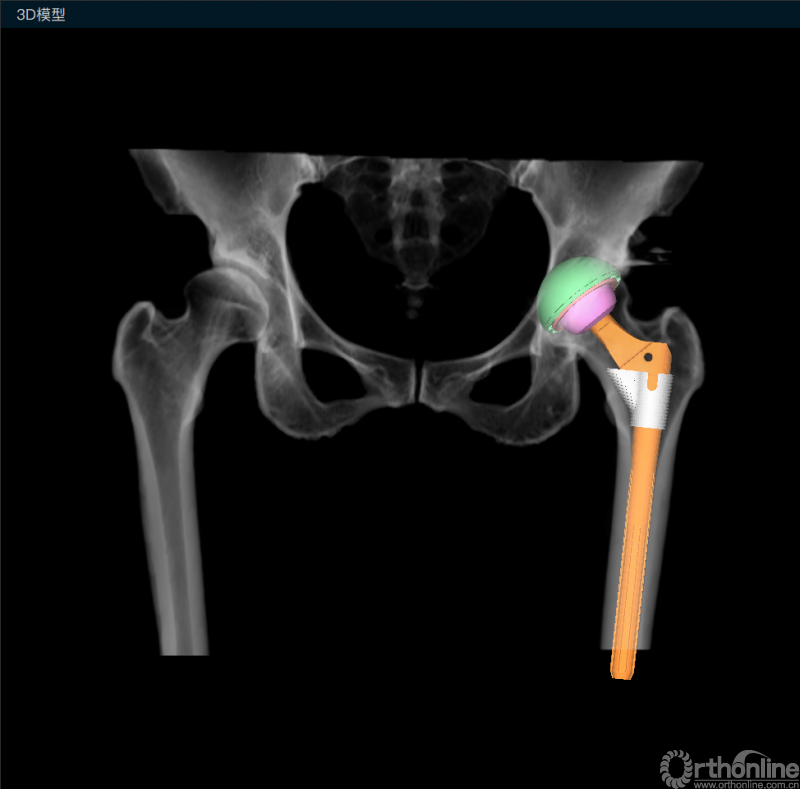

规划完成三维效果图

术前使用最新发布的AI HIP 2.0-人工智能复杂全髋关节置换术规划系统,对该患者手术进行规划,该系统可根据患者术前骨盆CT图像,智能识别解剖位点,并根据股骨及髋臼的解剖形态,智能匹配得到相应型号大小的S-ROM假体以及安放位置,充分发挥S-ROM假体的优势。术者还可根据需要对股骨柄假体前倾角度、袖套大小、位置等进行微调,以实现最佳的假体安放效果。